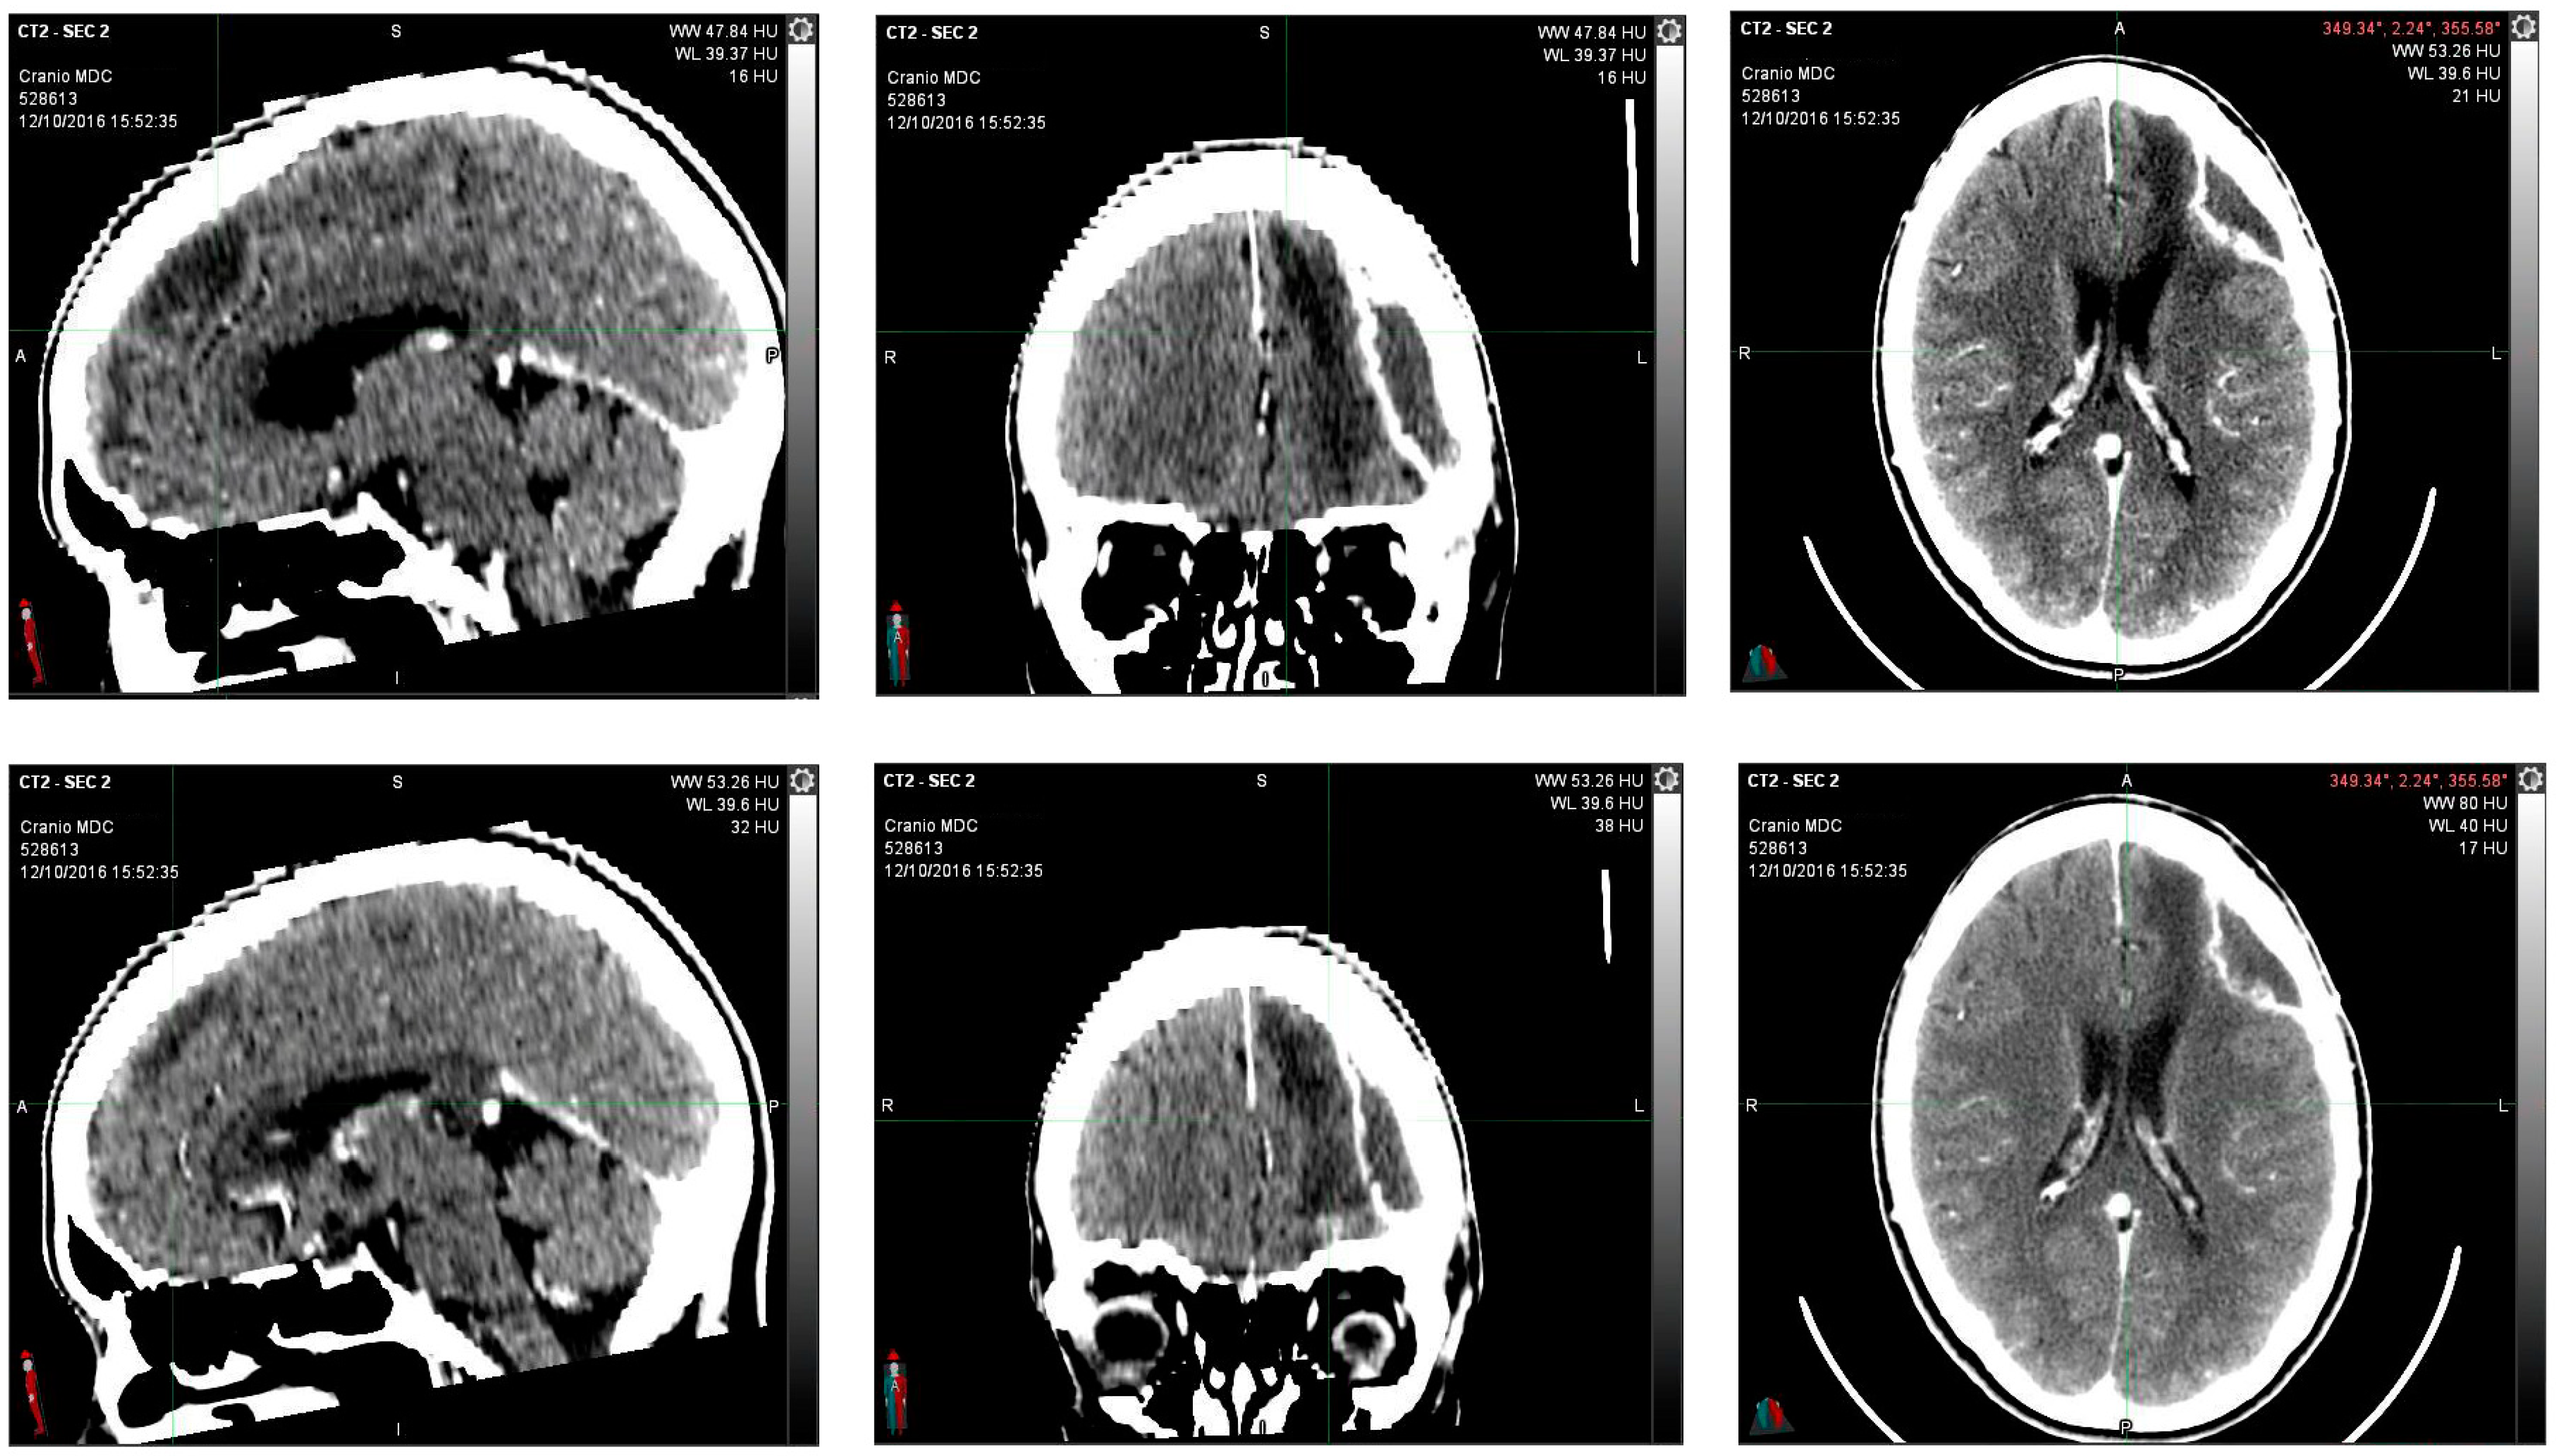

Encephalon/Cranium CT scan with contrast medium performed postoperatively on 12 October 2016 showed an apparently reduced liqueur-like collection with associated wall impregnation. Posterior to the surgical cavity, there is an approximately 2 cm hyperdense solid nodule characterized by contrast-enhancing impregnation (Figure 2).

Figure 2.

12 October 2016, instrumental examination after partial removal of left frontal multicentric neoplasm. The CT scan images with contrast medium showed an apparently reduced liqueur-like collection with associated wall impregnation. Posterior to the surgical cavity, there is an approximately 2 cm hyperdense solid nodule characterized by contrast-enhancing impregnation.